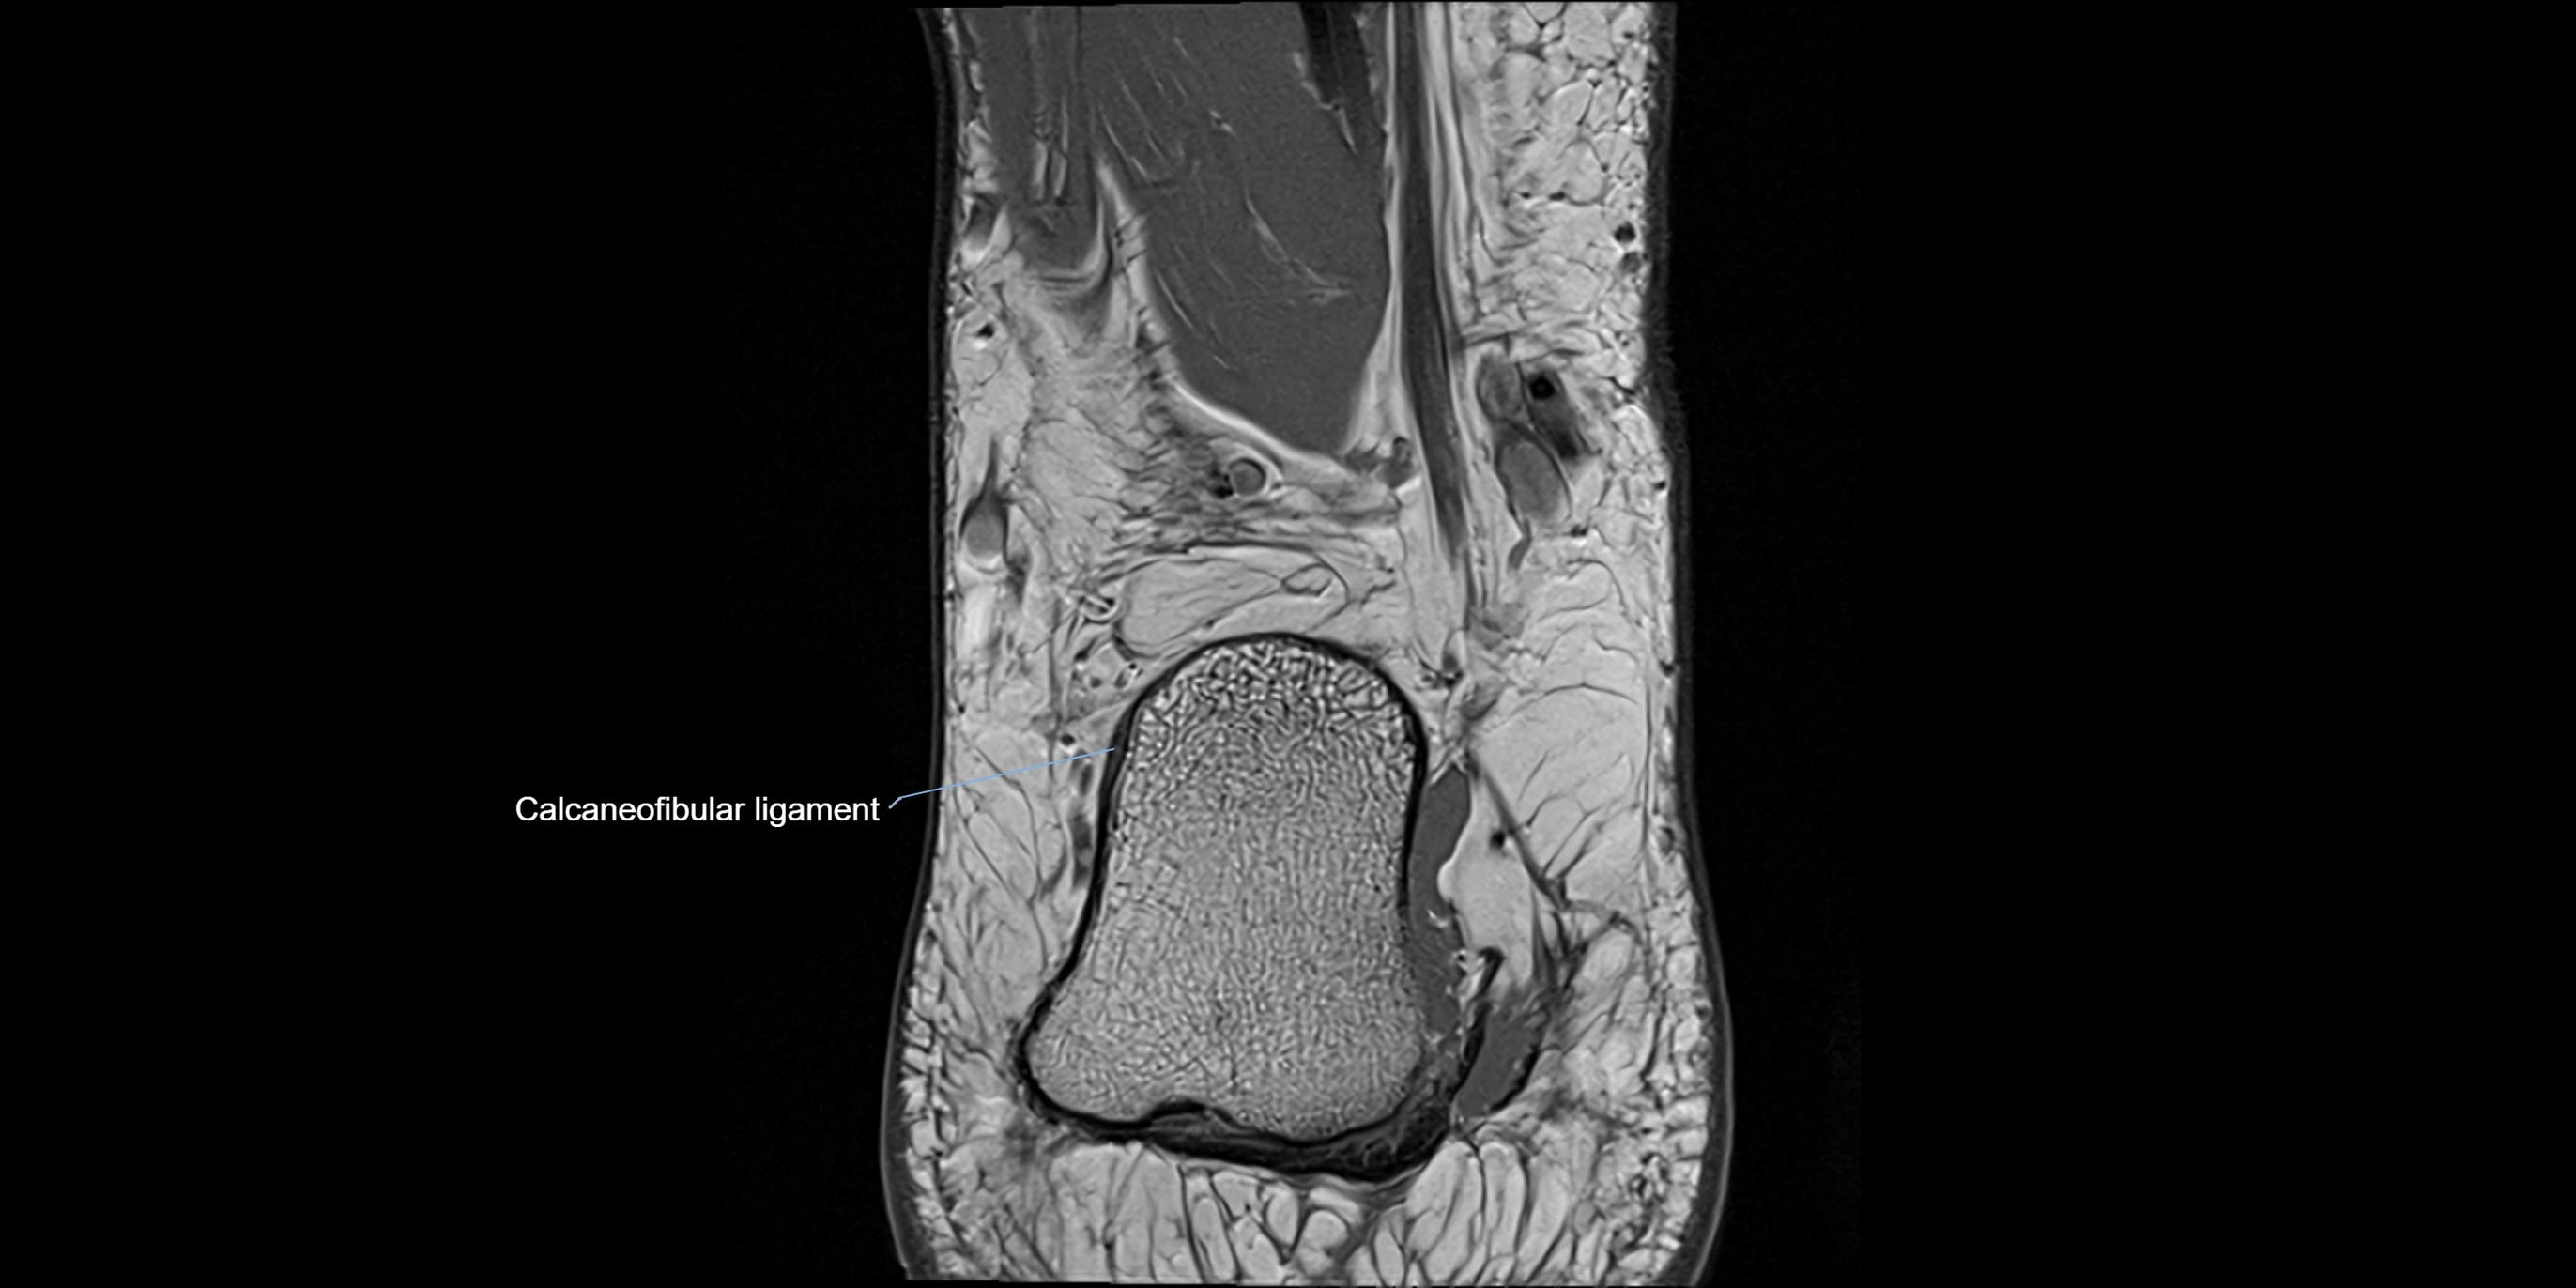

MRI image

image